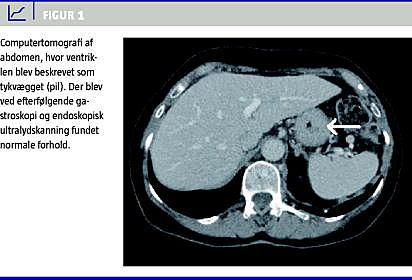

Da vi på vores afdeling havde haft fornemmelsen af et stigende antal henvisninger til endoskopisk ultralydskanning (EUS), efter at man på CT af abdomen tilfældigt havde opdaget/beskrevet, at ventrikelvæggen var fortykket, hvorfor der var rejst mistanke om malign sygdom i mavesækken (Figur 1 ), besluttede vi os for at gennemgå litteraturen for at se, hvor stor denne risiko var, og samtidig vurdere, hvorledes denne problemstilling mest rationelt kan afklares.